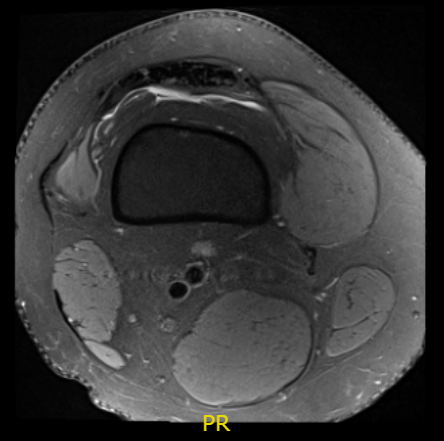

MRI result received, there is status post anterior cruciate ligament reconstruction. The graft is intact. Tubular cyst formation is present within the tibial tunnel. There is a large bucket-handle tear of medial meniscus, displaced into the intercondylar notch and over anterior horn.

There is a tiny capsule remnant posteriorly and peripherally. The lateral meniscus demonstrates free margin fraying of posterior horn and adjacent body aspect without substance tear.